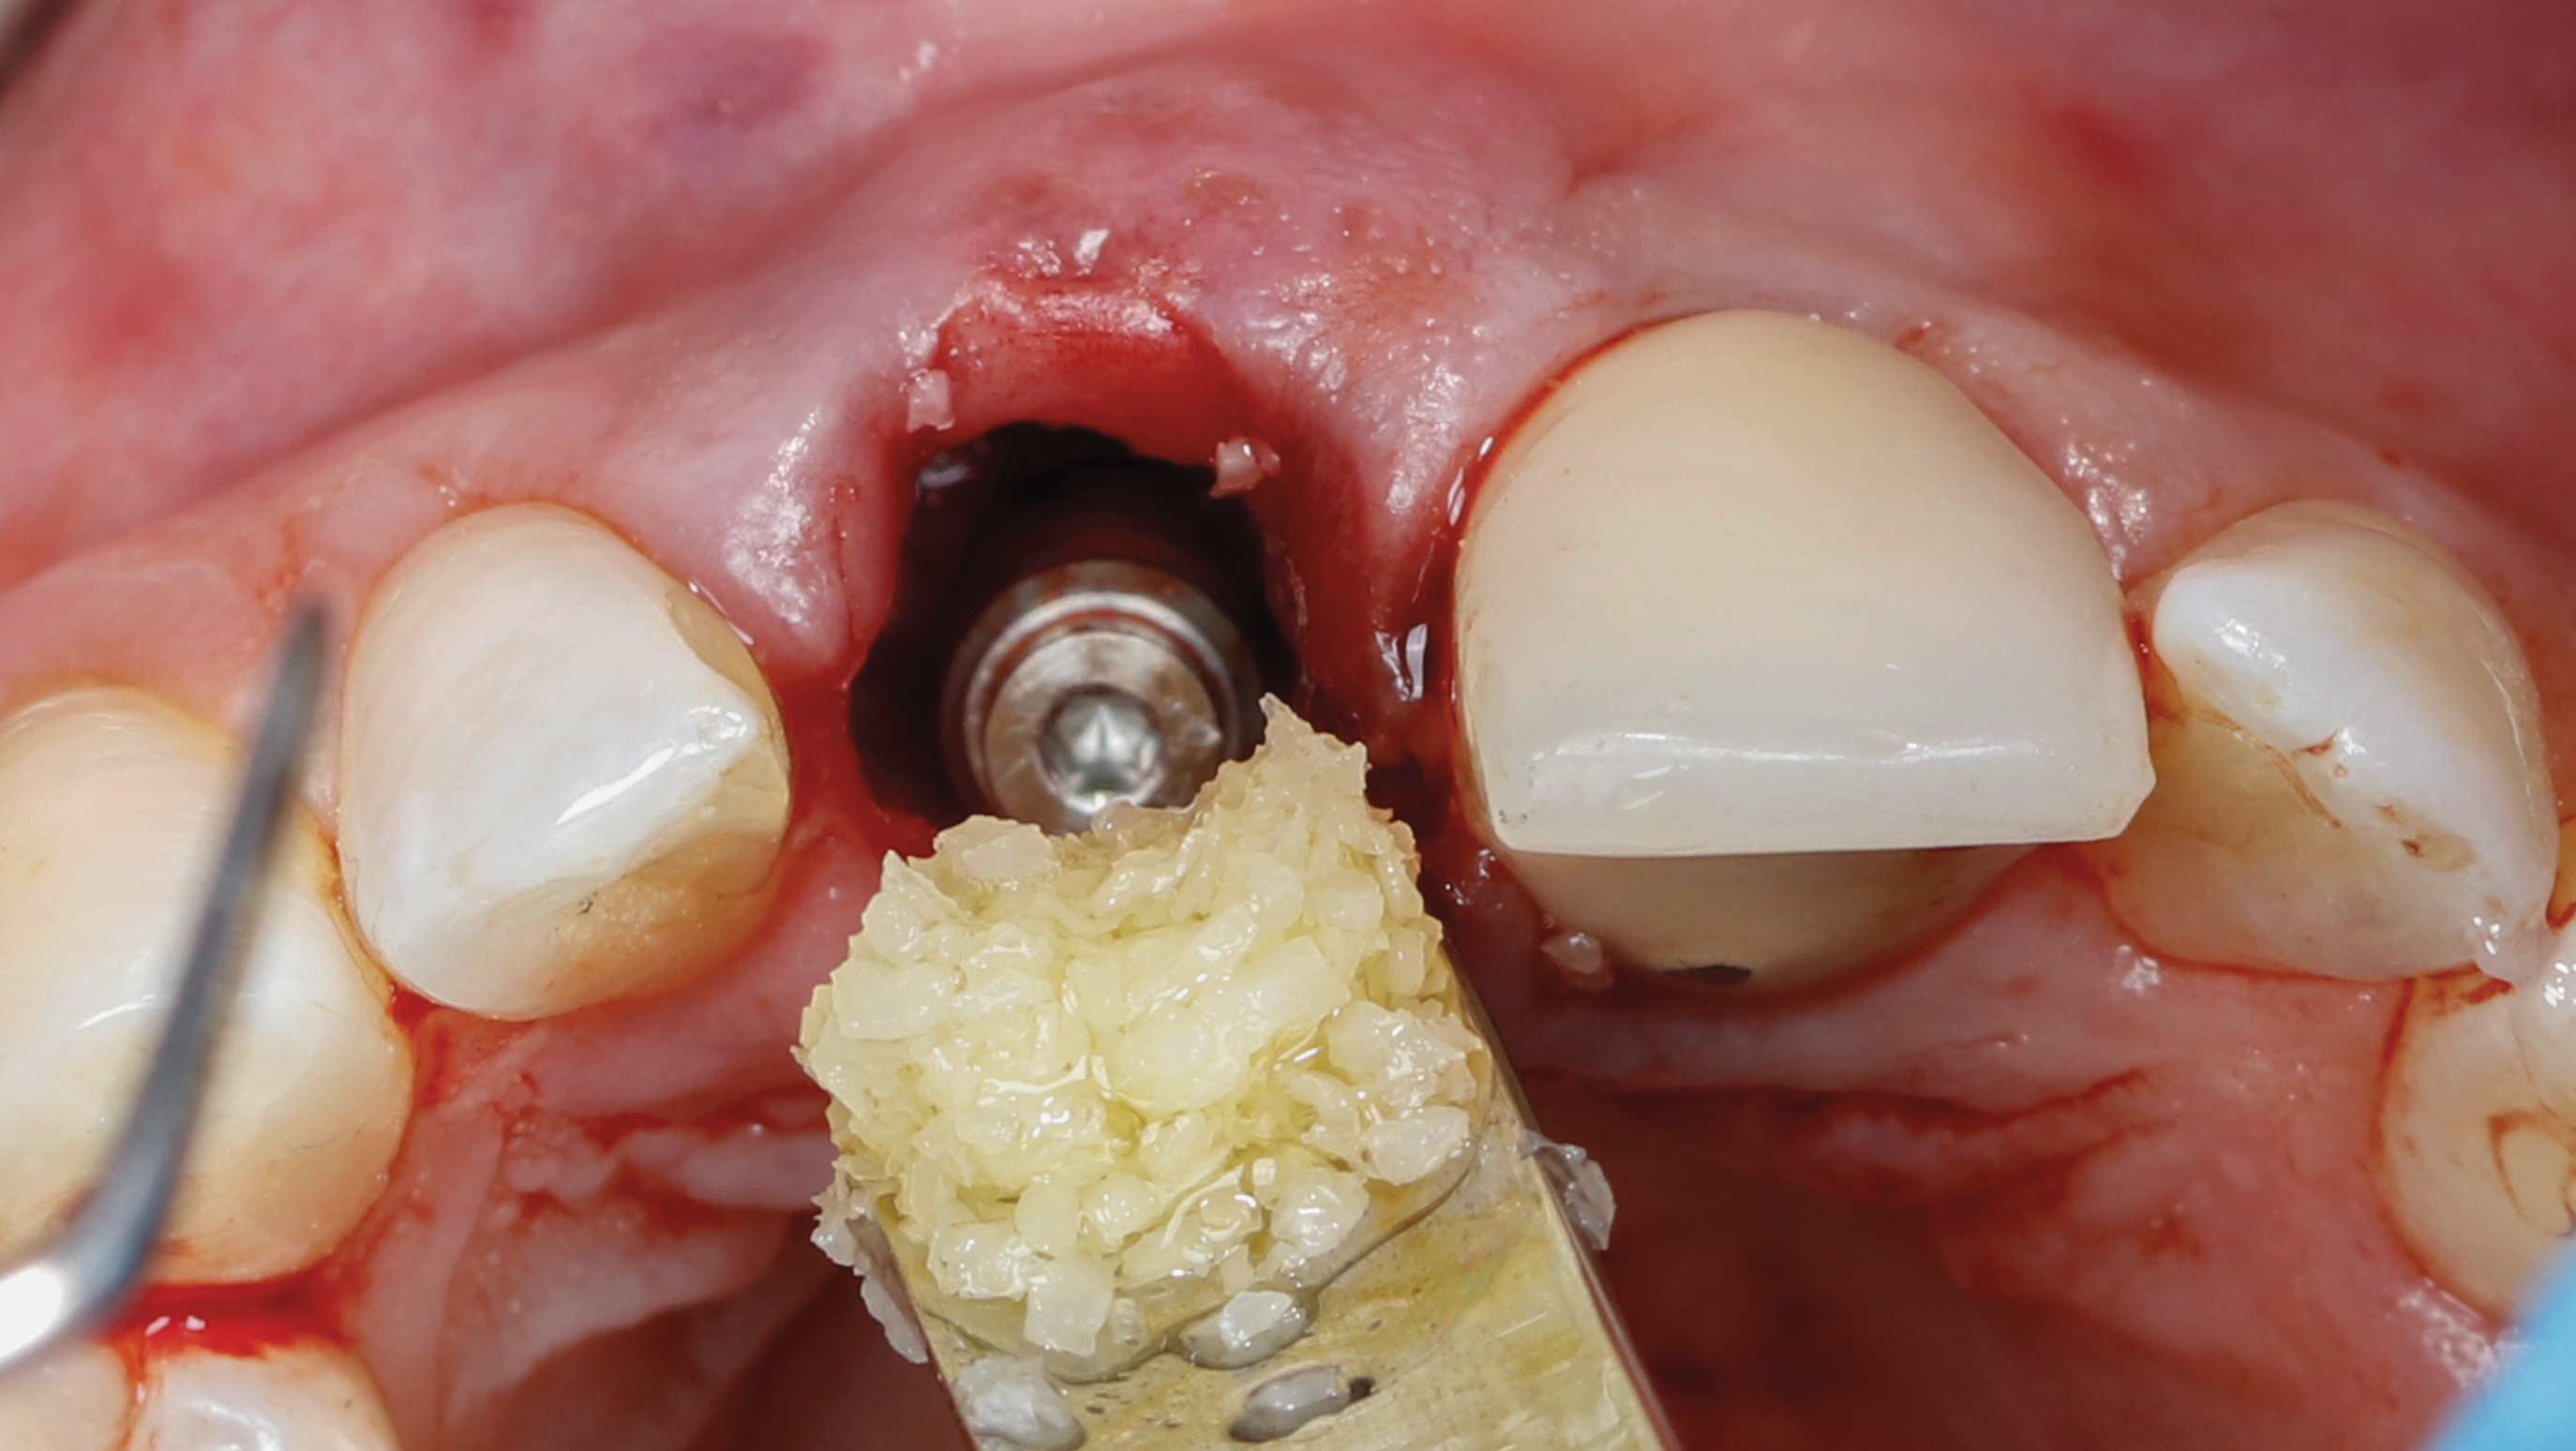

Fig 15. SPOT Step 6: The implant is placed to the preplanned depth in the implant osteotomy, and the jumping gap is grafted.

Figure 15